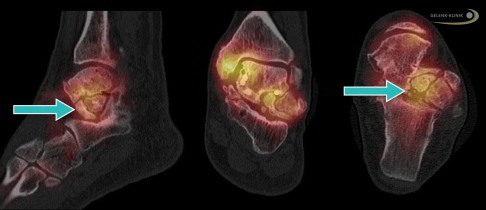

Besonders hilfreich für die Untersuchung von Knochenveränderungen sind Schnittbildverfahren, die mit Röntgenstrahlung arbeiten. Neben dem Kernspin (MRT) und SPECT ist besonders die digitale Volumentomographie (DVT) des Sprunggelenks wertvoll, um die charakteristischen Veränderungen im Innern des Sprungbeins darzustellen.

Die Knochenszintigrafie ist durch ihre verschiedenen Aufnahmezeiten ebenfalls hilfreich. Sie hilft dem behandelnden Orthopäden, die Verteilung der Nekrose und auch die Risiken einer Frakturierung besser abschätzen zu können.

Nach einem Kollaps des Knochens unter dem Gelenkknorpel (subchondraler Knochen) kann nur das DVT (digitale Volumentomografie) die genaue Lage und Belastung der Knochenstrukturen darstellen. Das Röntgenbild als Überlagerungsbild ist ebenfalls eine gute Möglichkeit, die häufig aber – anders als die hochauflösende röntgenbasierte Schnittbilddiagnostik wie DVT oder CT – nicht die gesamte Situation der Strukturen darstellt. Daher ist ein Röntgenbild für eine Therapieentscheidung oft nicht ausreichend.